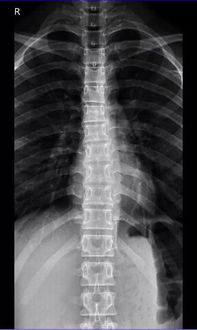

在X光片上,医生们惊讶地发现张先生的肺部竟然有一个金属异物——一个鱼钩,这个鱼钩位于张先生的右下肺叶,显然已经存在了一段时间,这一发现立即引起了医生们的警觉,他们迅速将张先生转入急诊室进行进一步的检查和评估。

急诊医生立即对张先生进行了全面的体检,并安排了CT扫描以更清晰地显示鱼钩的位置和周围的情况,CT结果显示,鱼钩已经穿透了张先生的肺部,并可能导致了局部的感染,医生们迅速制定了手术计划,准备将鱼钩取出,以防止其进一步移动并造成更严重的后果。